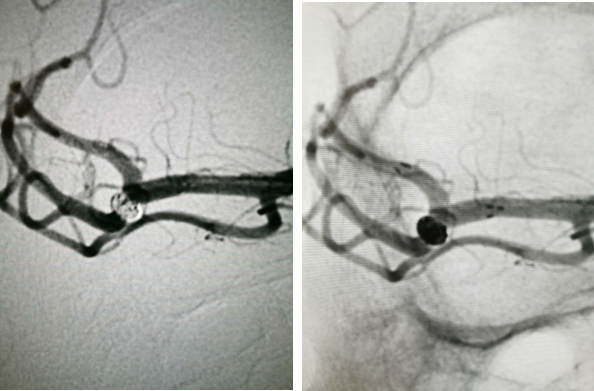

全脑血管造影:右侧大脑中动脉M1分叉处动脉瘤,瘤体3.3 mm*4.1 mm,瘤颈2.7 mm。前交通动脉瘤栓塞完全。

全麻满意后,常规消毒铺巾,采用改良 Seldinger技术穿刺右侧股动脉成功,置入6F动脉鞘。黑泥鳅导丝带领5F单弯导管行脑动脉造影,右侧颈内动脉造影见:右侧大脑中动脉M1分叉处动脉瘤,瘤体3.3 mm*4.1 mm,瘤颈2.7 mm。前交通动脉瘤栓塞完全。

经右侧股动脉鞘,黑泥鳅导丝带领导引导管(Codman 6F Envoy DA)到达右侧颈内动脉岩段,微导丝(Synchro--14 0.014 in*200 cm)带领支架微导管(Excelsior SL--10)到达右侧大脑中动脉M2段,退出微导丝。微导丝带领弹簧圈微导管(Echelon10)到达右侧M1远端分叉处动脉瘤内,退出微导丝。经弹簧圈微导管填入弹簧圈(Codman 3 mm*4 cm)经支架微导管输送支架(Neuroform Atlas 3.0 mm*15 mm)并释放在M2段至M段中部,完全覆盖动脉瘤颈。继续经弹簧圈微导管依次填入弹簧圈数枚,间断造影确保右侧大脑中动脉及远端血流通畅。右侧颈内动脉造影确认:动脉瘤致密填塞,载瘤动脉通畅,手术结束。有侧股动脉穿刺处用血管封堵器封堵,并压迫器持续压迫。术后患者麻醉清醒,拔除气管插管,呼唤应答,对答切题,言语清楚,四肢肌力肌张力正常。安返病房。